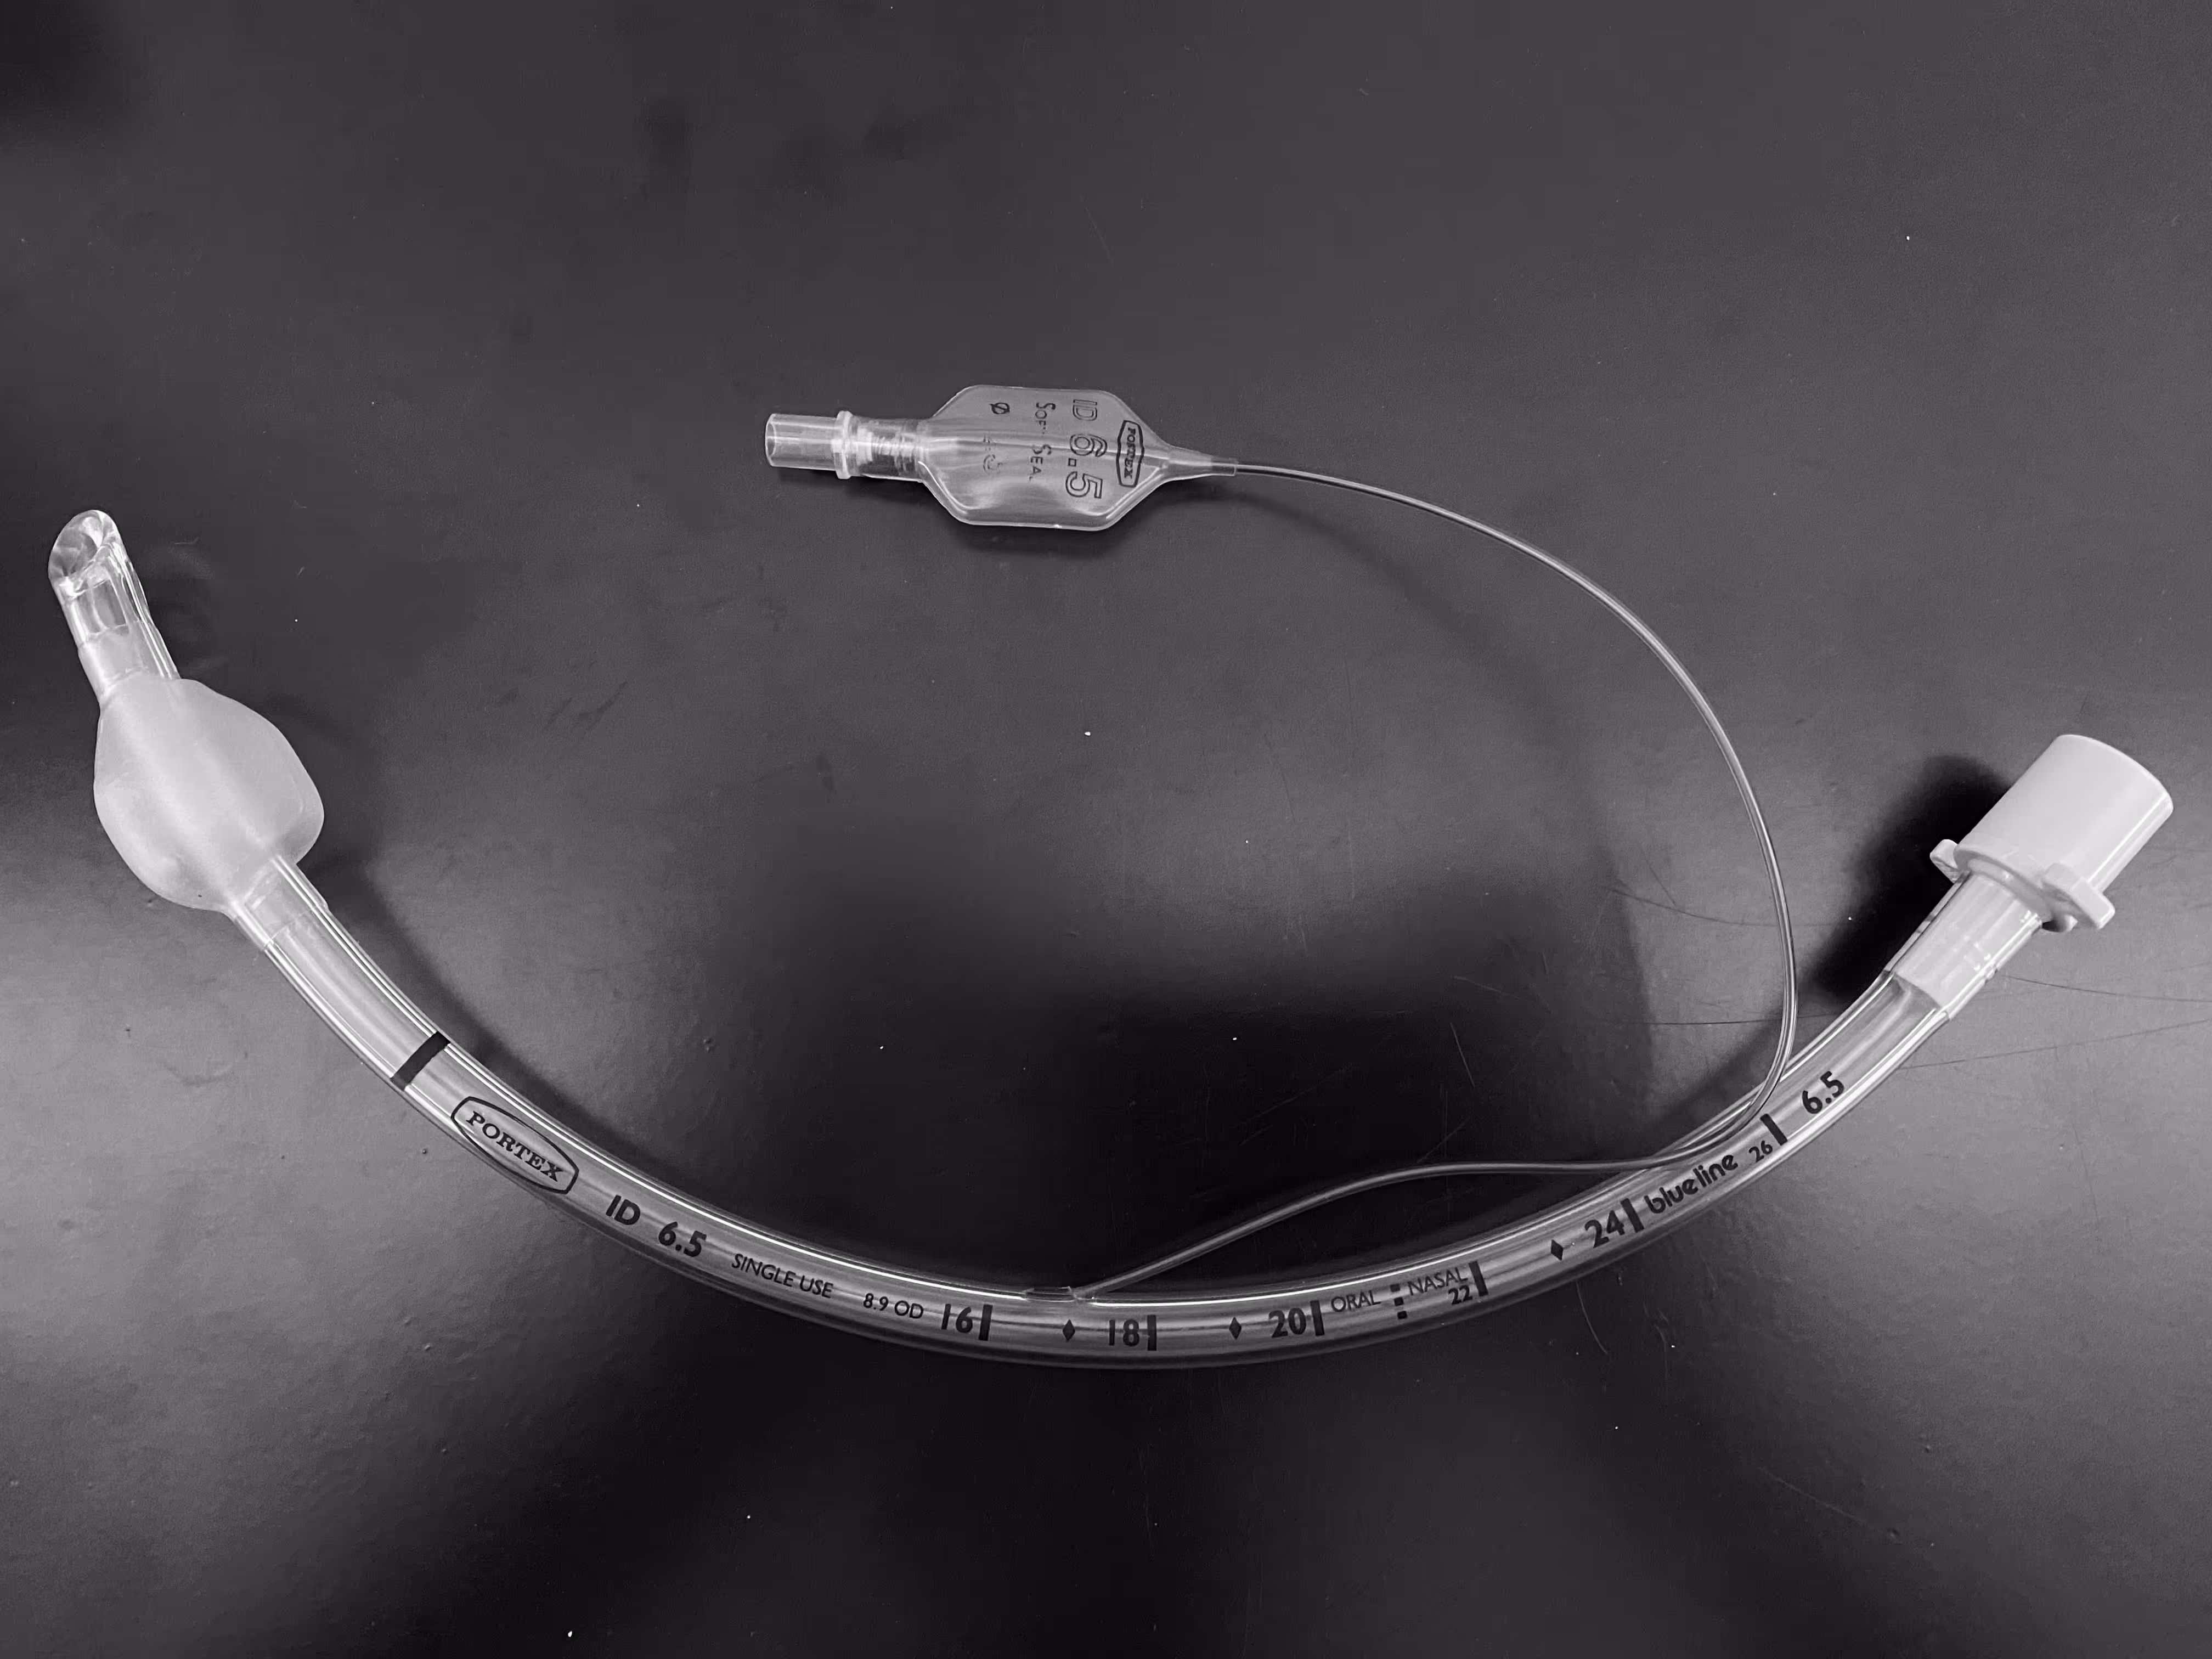

We have developed a series of  eLearning materials to facilitate student learning of radiographic assessment of lines and tubes and their potential complications.In this project, lines and tubes covered include: percutaneous central venous catheters, Port-a-Caths, Hickman lines, peripherally inserted central venous catheters (PICC lines), endotracheal tubes(ETT), amongst others.

The animated videos with voiceover cover relevant anatomy for lines and tubes radiographic assessments, a step-by-step walkthrough of the radiological interpretation of line positioning that highlights the important aspects, potential pitfalls, and complications in each step of the assessment. The video content suits students of varying degrees of proficiency on the topic and supplements conventional lectures by acting as bite-sized refreshers on the topic.

A flipping card game to associate the purposes and appearances of different lines and tube type